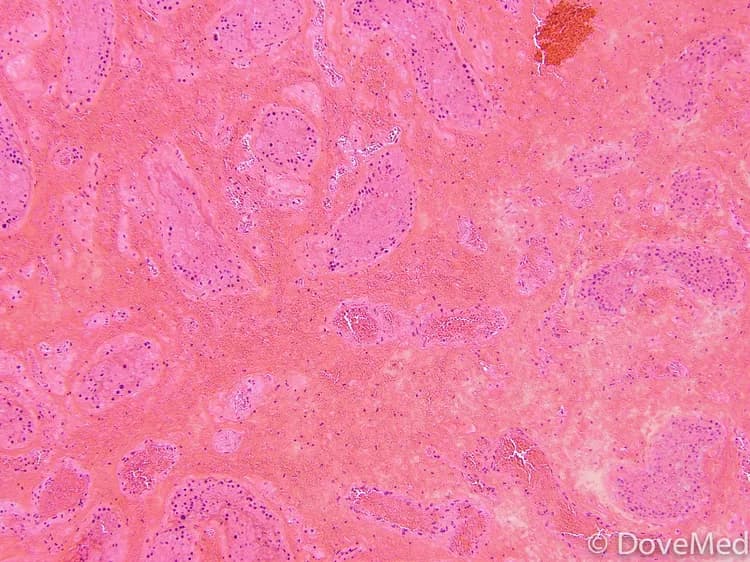

• Testicular Torsion is a medical emergency in which the testicle rotate and cause the spermatic cord (the cord which supplies blood to the scrotum) to bend and twist, leading to a condition termed as ischemia. ‘Ischemia’  means the cutting-off of the blood supply, in this case, to the testicles

• Testicular Torsion is a medical condition that occurs due to a rotation of the testicles, causing the spermatic cord to twist itself, thereby preventing blood flow to the scrotum

• The testicular defect may occur sometimes due to Bell Clapper deformity, a congenital defect, in which the testis is not properly attached to the scrotum. This causes the testicles to move around freely inside the scrotum. Bell Clapper deformity usually causes bilateral Testicular Torsion, meaning that both the testicles are affected